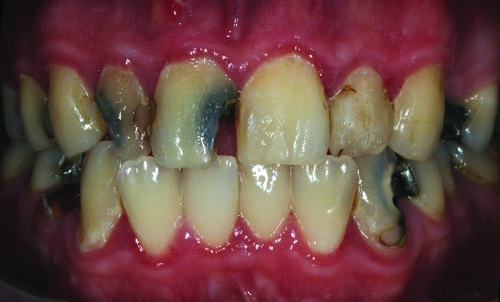

Fig. 2: Close-up retracted facial view of the patient’s upper and lower arches reveals extensive decay, missing teeth and obvious gingival inflammation.